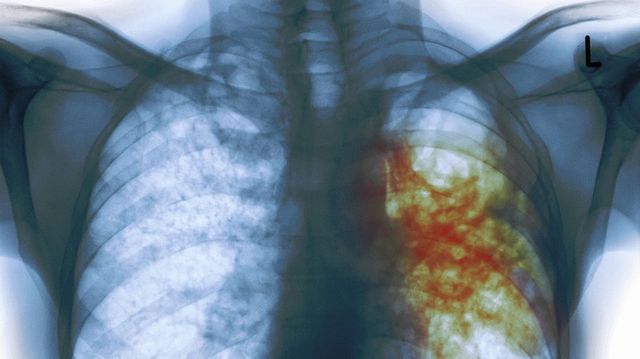

В Кременчуге у кассира в супермаркете диагностировали открытую форму туберкулеза

В Кременчуге у кассира крупной торговой сети супермаркетов медики диагностировали открытую форму туберкулеза, сообщает Кременчугская газета со ссылкой на информацию руководителя городской санэпидслужбы Василия Товстого.

По словам специалистов, сотрудница супермаркета обратилась в медучреждение, почувствовав недомогание. Данные анализов подтвердили диагноз — туберкулез.

Как стало известно, обследование на флюорографе, которое каждый должен делать ежегодно, женщина не проходила уже 8 лет.

Как с отсутствием элементарных данных медосмотра женщина работала в супермаркете, в данный момент выясняют контролирующие органы. супермаркет ждут дополнительные проверки.